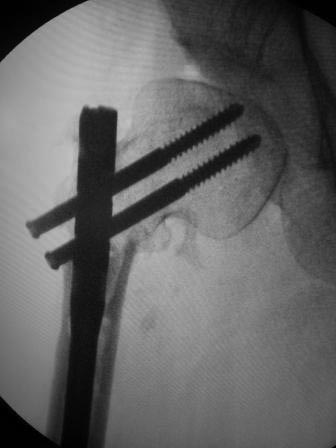

Уважаемые коллеги. Больная оперирована 06.03.15г клинок был сломан,

и пока его с трудом  удалили  от неполноценного вертела почти ничего не

осталось,сломанный шуруп тоже удален, шейка совсем короткая, , ШДУ

около 95гр, из-за сильного остеопороза при сверление в положении чуть

вальгуса наружная стенка крошится , и еще что интересно при первой

операции головка бедра оказалось фиксирован в положении ретроверсии

примерно 10-15 гр.. и с трудом удалось выпрямить головку и шейку до 0

гр. , укорочение было чуть больше 1см , п/о -2см, пока фиксация гипсовый

сапожок с деротатором. Дальше как быть? Может временно фиксировать